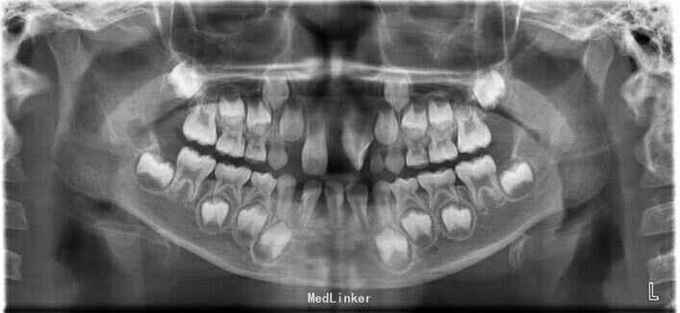

儿童矫正一例

患者,男,10岁,矫正牙齿正常